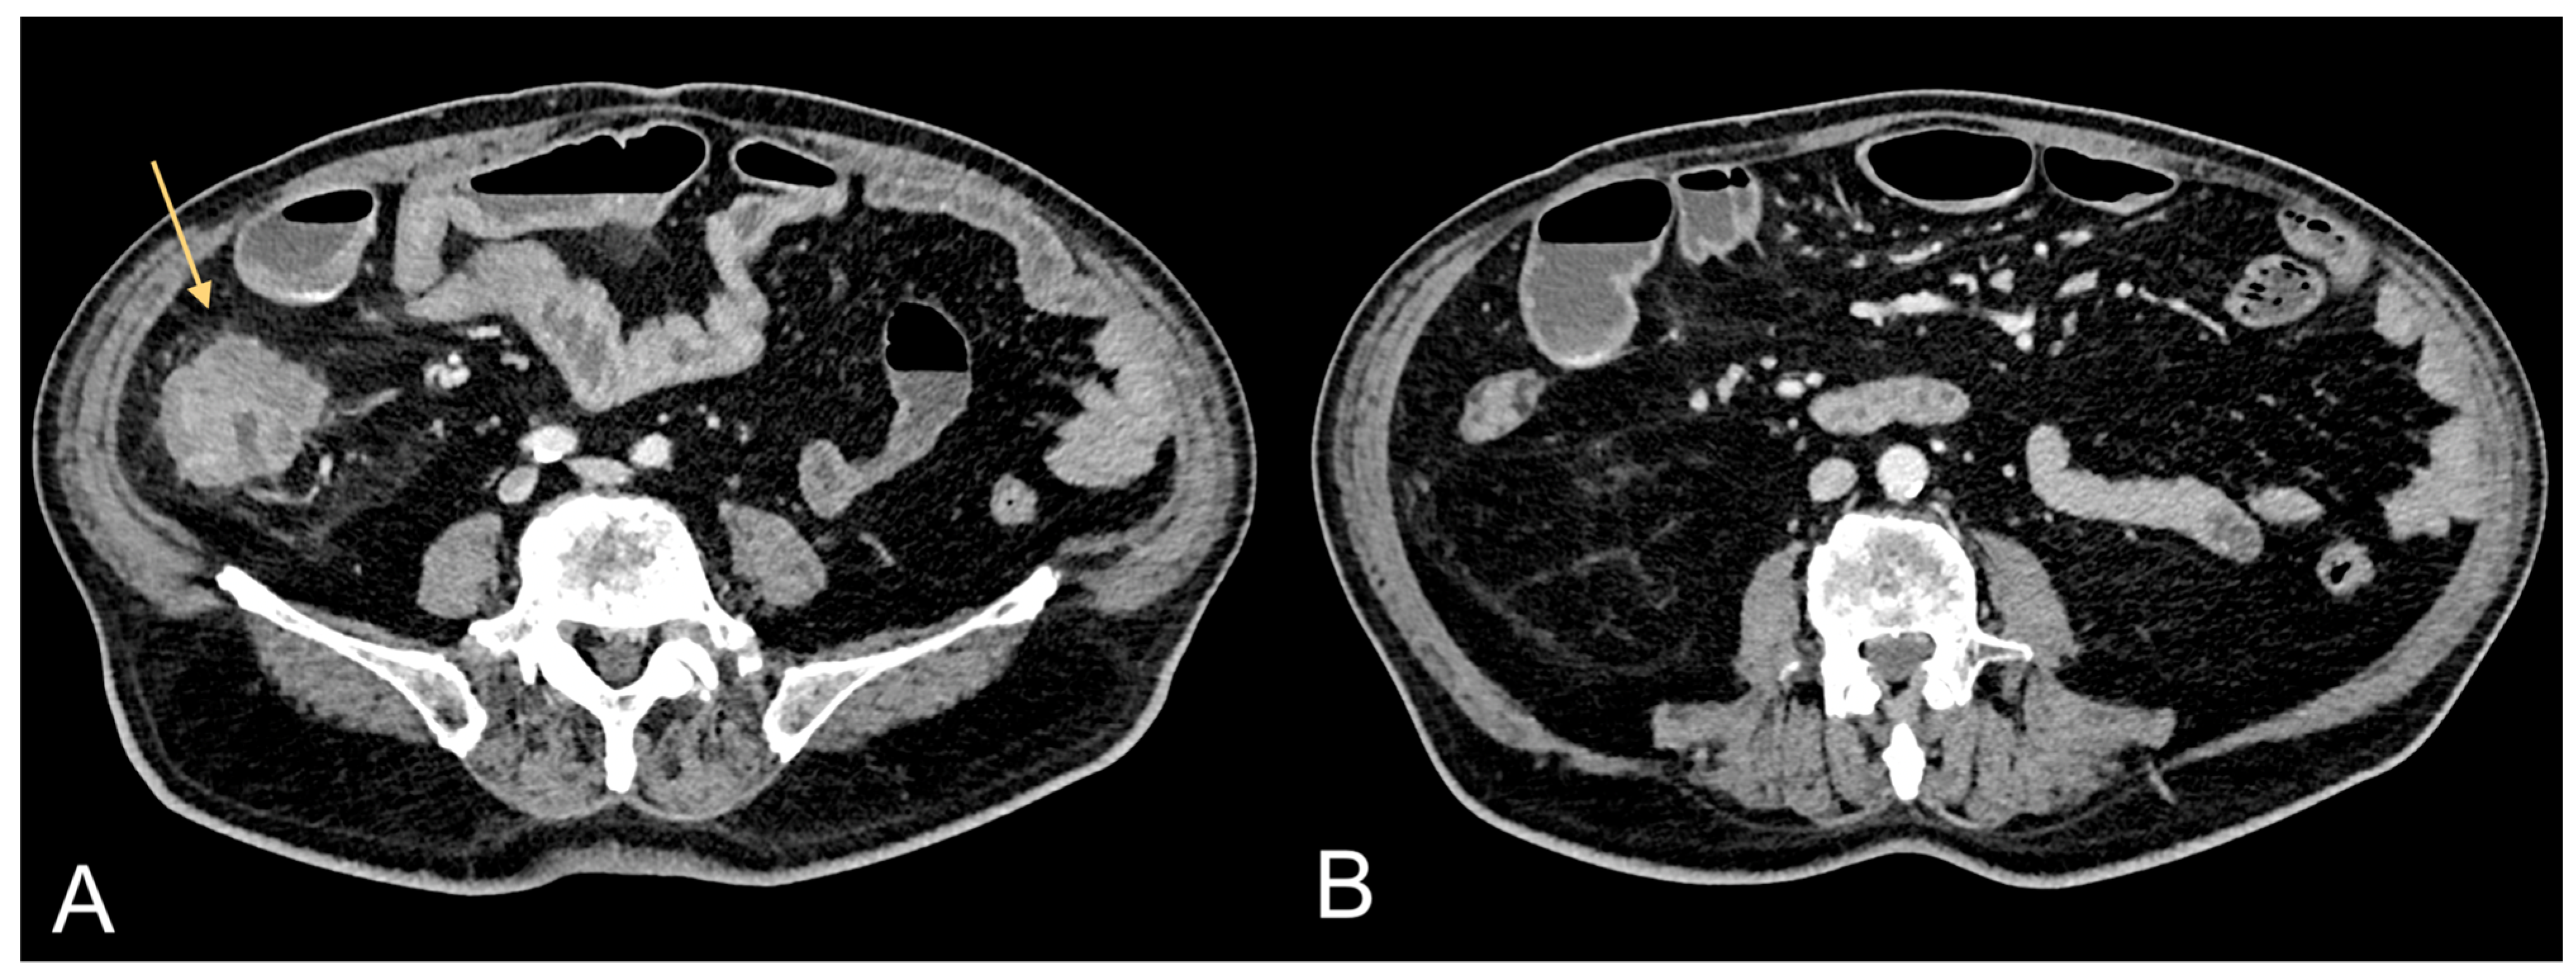

Figure 1.

Contrast-enhanced CT images of a 75-year-old male patient showing CRC (light orange arrow in (A)) and associated excessive amount of VAT (B).